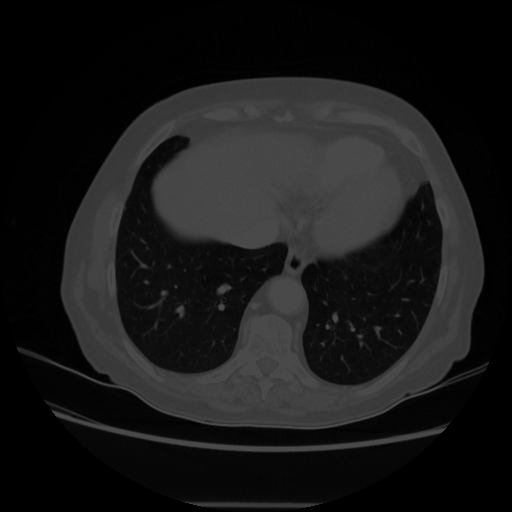

Original VENOUS CT scan

Full window (WL 1023.5, WW 4095 β†’ Low βˆ’1024, High +3071)

Lung window (WL -600, WW 1500 β†’ Low βˆ’1350, High +150)

Mediastinum window (WL 40, WW 400 β†’ Low βˆ’160, High +240)